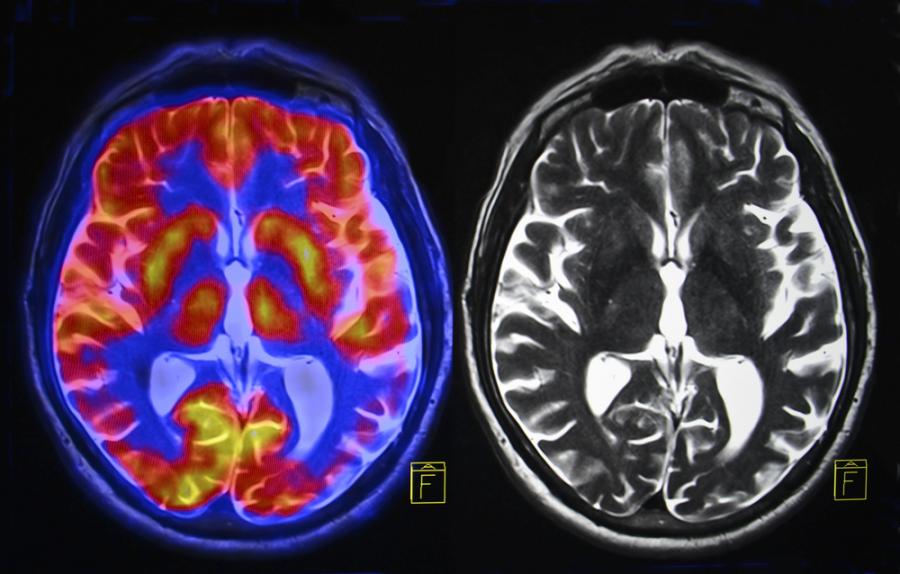

Най-мощният в света апарат за ядрено-магнитен резонанс направи първи изображения на човешкия мозък и вече е готов да даде по-добра представа за неговото функциониране, както и за някои невродегенеративни и психиатрични заболявания, предаде АФП.

Магнитната индукция достига 11,7 тесла, което дава възможност да се получат десет пъти по-прецизни изображения от тези в болниците, където мощността на магнитно-резонансните скенери не надвишава 3 тесла.

"С тази машина можем да видим малките съдове, които захранват черепната кора, или детайли от малкия мозък, които досега бяха почти невидими", коментира Виньо.